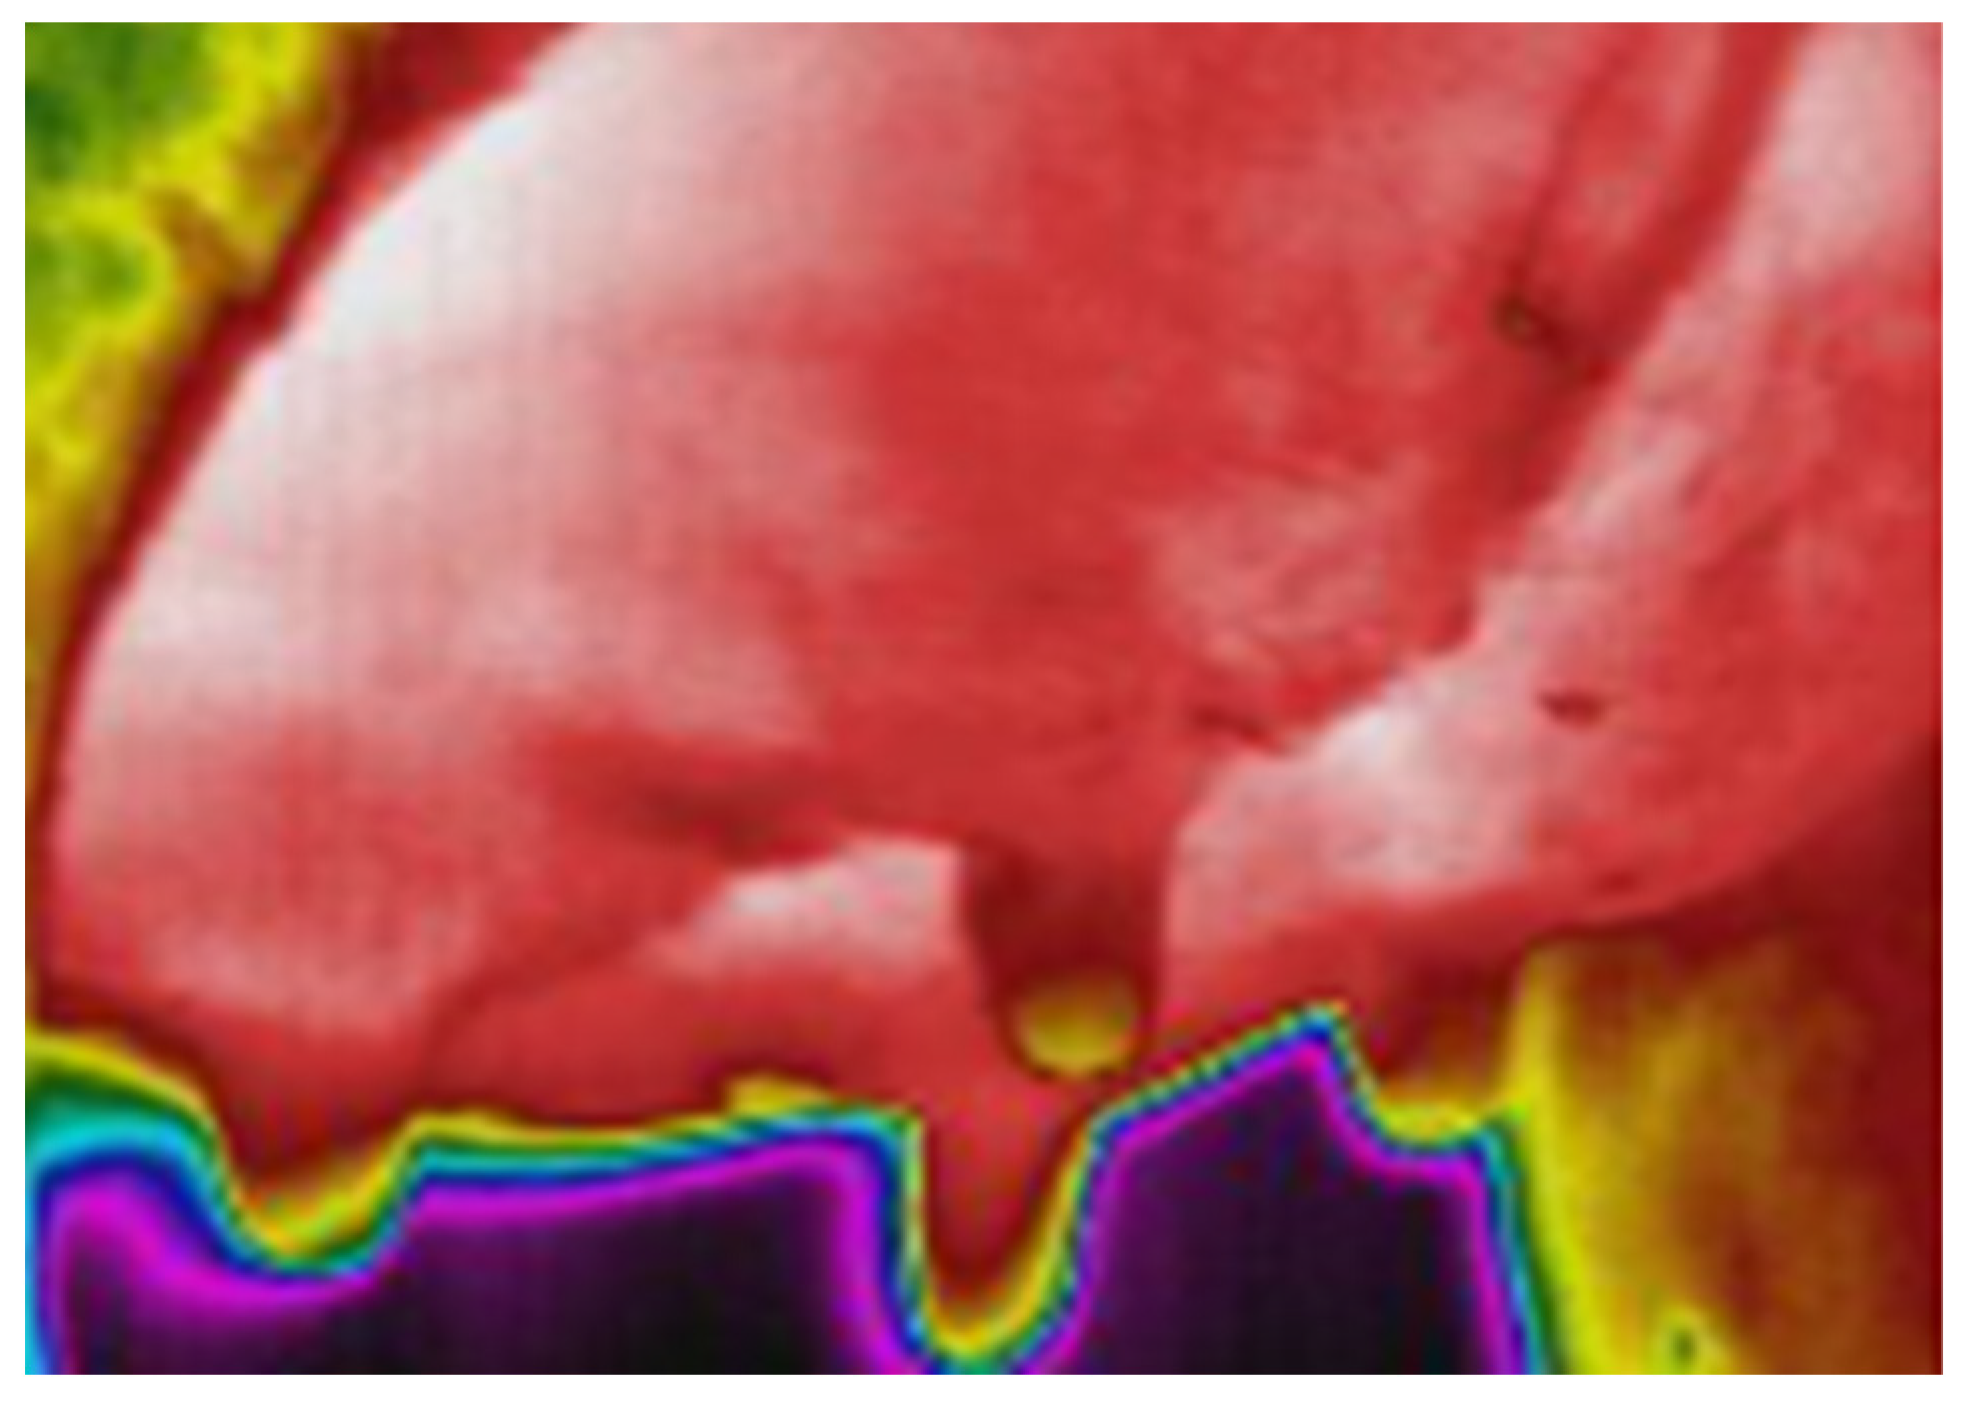

- Zaninelli, M.; Redaelli, V.; Luzi, F.; Bronzo, V.; Mitchell, M.; Dell’Orto, V.; Bontempo, V.; Cattaneo, D.; Savoini, G. First Evaluation of Infrared Thermography as a Tool for the Monitoring of Udder Health Status in Farms of Dairy Cows. Sensors 2018, 18, 862. [Google Scholar] [CrossRef] [PubMed]

- Metzner, M.; Sauter-Louis, C.; Seemueller, A.; Petzl, W.; Klee, W. Infrared Thermography of the Udder Surface of Dairy Cattle: Characteristics, Methods, and Correlation with Rectal Temperature. Vet. J. 2014, 199, 57–62. [Google Scholar] [CrossRef] [PubMed]

- Colak, A.; Polat, B.; Okumus, Z.; Kaya, M.; Yanmaz, L.E.; Hayirli, A. Short Communication: Early Detection of Mastitis Using Infrared Thermography in Dairy Cows. J. Dairy Sci. 2008, 91, 4244–4248. [Google Scholar] [CrossRef]

- Sathiyabarathi, M.; Jeyakumar, S.; Manimaran, A.; Jayaprakash, G.; Pushpadass, H.A.; Sivaram, M.; Ramesha, K.P.; Das, D.N.; Kataktalware, M.A.; Prakash, M.A.; et al. Infrared Thermography: A Potential Noninvasive Tool to Monitor Udder Health Status in Dairy Cows. Vet. World 2016, 9, 1075–1081. [Google Scholar] [CrossRef]

- Machado, N.A.F.; Da Costa, L.B.S.; Barbosa-Filho, J.A.D.; De Oliveira, K.P.L.; De Sampaio, L.C.; Peixoto, M.S.M.; Damasceno, F.A. Using Infrared Thermography to Detect Subclinical Mastitis in Dairy Cows in Compost Barn Systems. J. Therm. Biol. 2021, 97, 102881. [Google Scholar] [CrossRef]